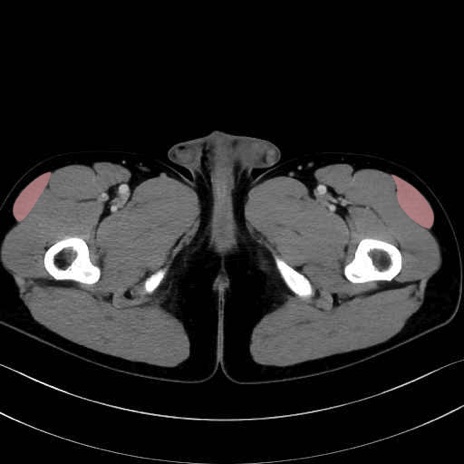

大腿筋膜張筋 (Tensor fasciae latae)